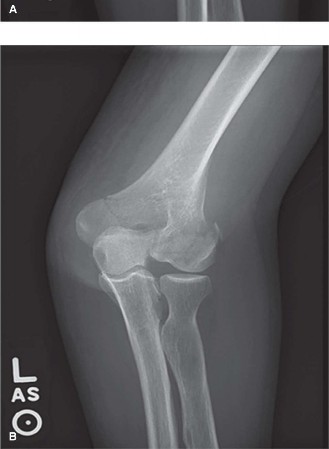

Distal humerus fractures (DHFs) represent a challenging subset of elbow trauma, accounting for approximately 2-7% of all adult fractures and up to 30% of elbow fractures. Their incidence exhibits a bimodal distribution: affecting younger individuals primarily due to high-energy trauma (e.g., motor vehicle accidents, falls from height) and the elderly population secondary to low-energy falls, often in the context of osteopenia or osteoporosis. The anatomical complexity of the distal humerus, involving the intricate articular surface of the trochlea and capitellum, coupled with the proximity of vital neurovascular structures, renders these injuries significant. Prognosis is heavily dependent on achieving and maintaining an anatomical reduction of the articular surface and stable fixation, allowing for early rehabilitation and restoration of functional range of motion (ROM).

- Standard Radiographs: Anteroposterior (AP), lateral, and oblique views of the elbow are the initial imaging modalities. These provide basic information regarding fracture type, displacement, and comminution.

- Computed Tomography (CT) Scan: Essential for complex intra-articular fractures (AO/OTA Type B and C). Fine-cut CT scans with 2D and 3D reconstructions provide invaluable detail regarding the articular surface, fragment orientation, and the extent of comminution. This allows for precise identification of the capitellum and trochlea fragments, guiding reduction strategy. Angiography may be indicated if a vascular injury is suspected (e.g., absent pulse, expanding hematoma).